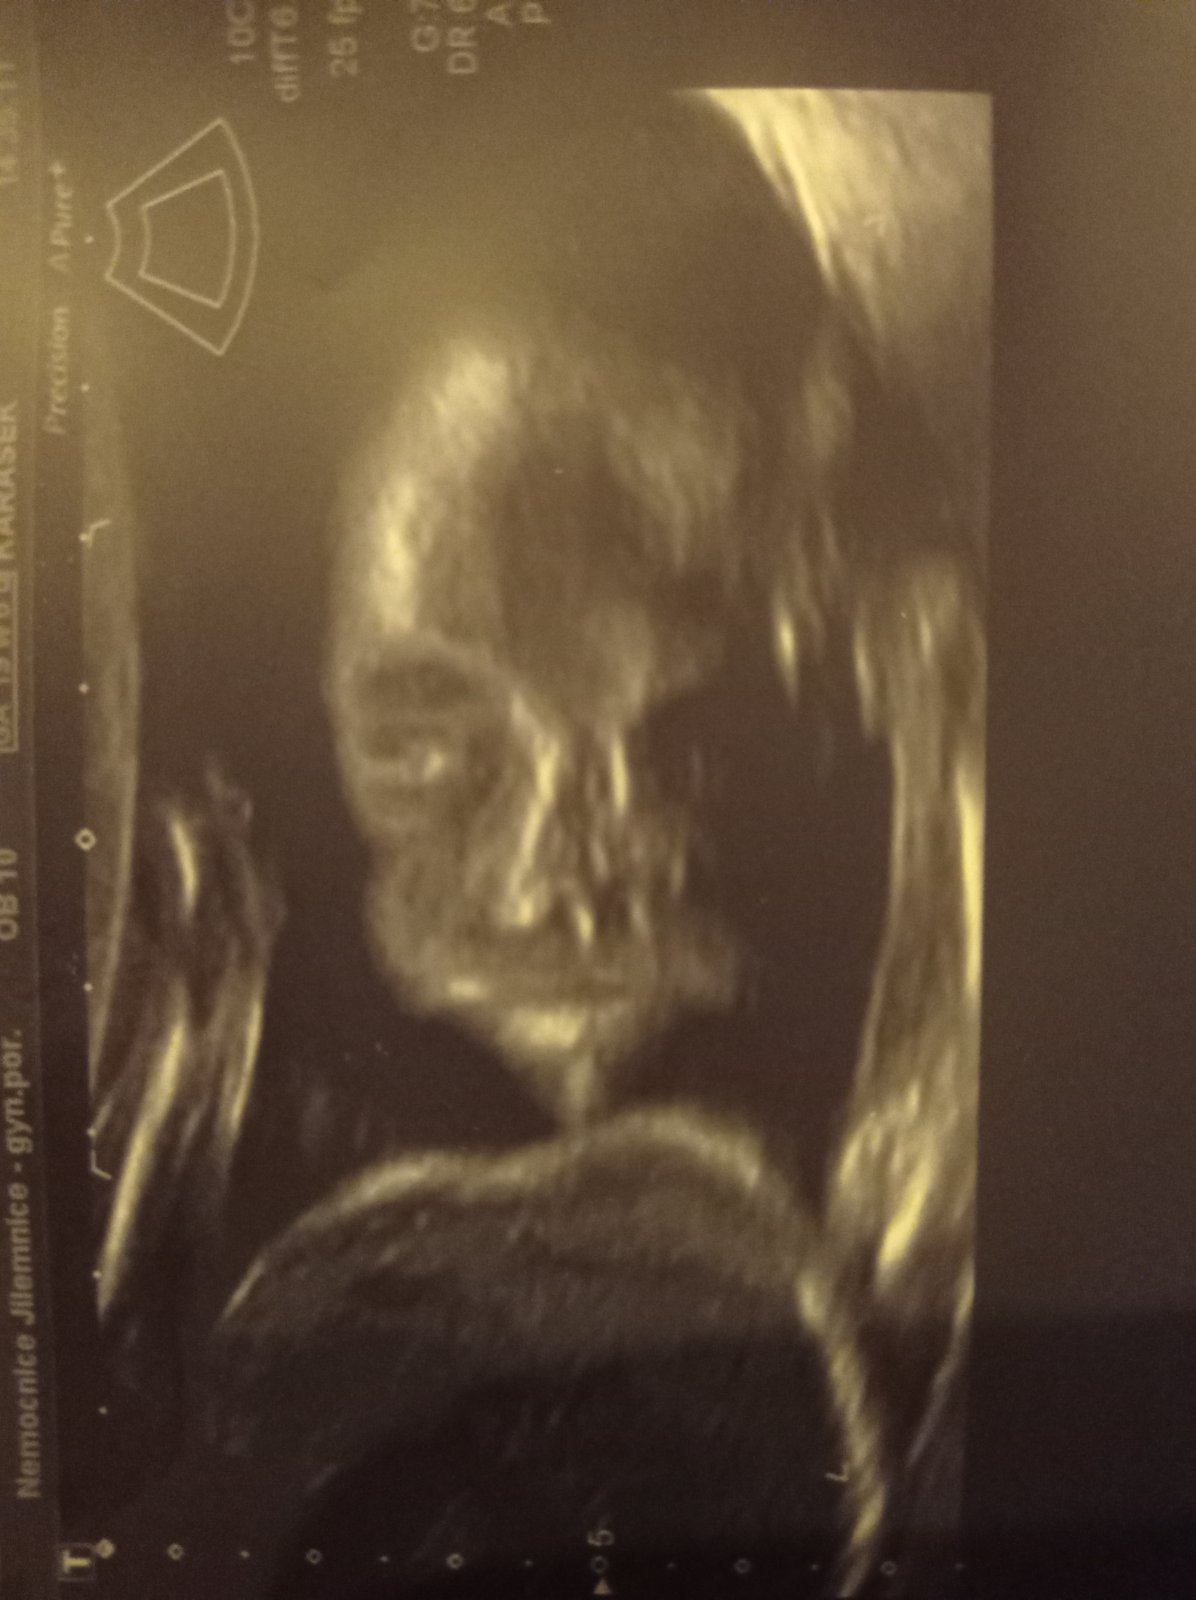

Já jsem z Harrachova, rodit budu v Jilemnici, kde jsem už rodila. První porod jsem měla vyvolávaný a nemám na něj příjemné vzpomínky. Takže bych se teď chtěla lépe připravit a poslouchám různá přípravná videa a diskuze o hypnoporodu. Jinak o té placentě taky teprve sbírám informace jak to chodí. Ale obty homeopatika bych fakt měla zájem, protože je to lék na několik let. Upřímně bych si taky asi nedala koktejl z placenty, který se taky dělá a prý náramně podporuje hojení po porodu a podporuje laktaci. Ale to už mi přijde dost....